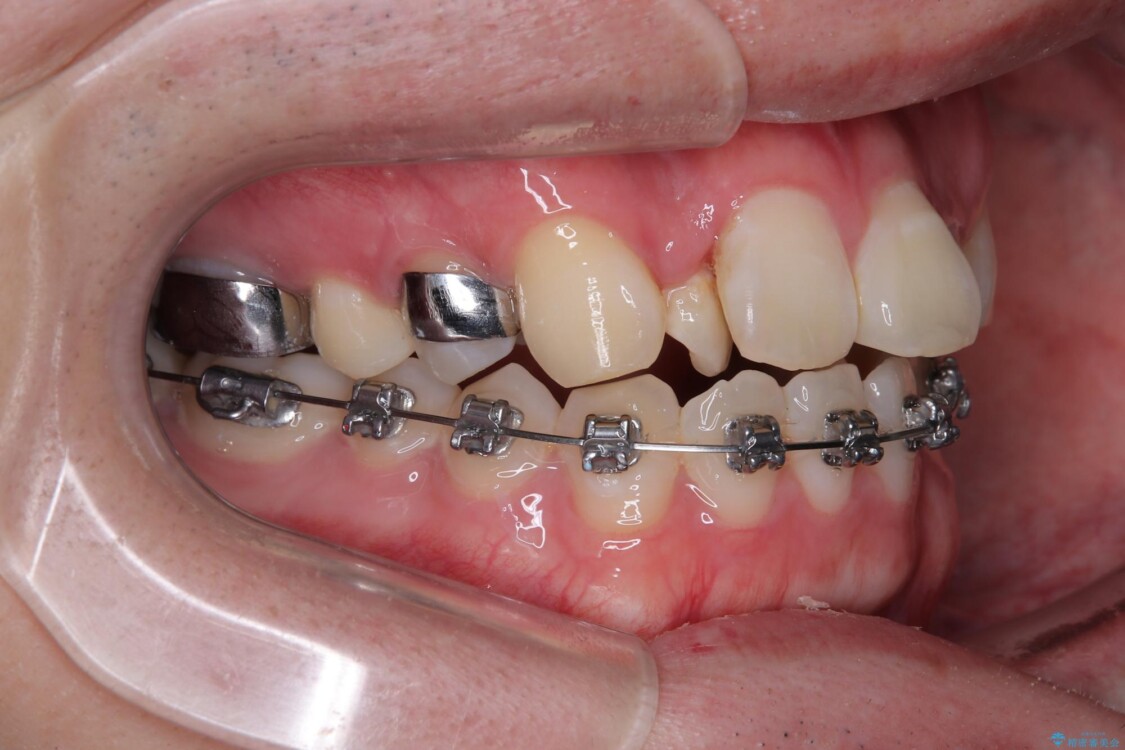

治療途中

• 1年でここまで変わる!歯列のがたつきと正中のズレを改善した矯正治療(メタルブラケット×MARPE) 治療途中画像